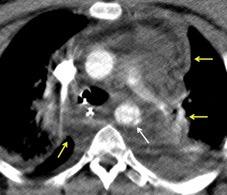

Síntomas y signos que se producen con la obstrucción total o parcial de la vena cava superior

Causas Malignas +/- 90-95%

Ca. Broncogénico (80-85%)

Linfoma No Hodgkin (15%)

Catéteres, shunts y marcapasos…23%

T. Mediastínico. Bocio

Fibrosis Idiopática

Tb, Histoplasmosis, Actinomicosis, Sarcoidosis

Carcinoma microcítico con síndrome de VCS